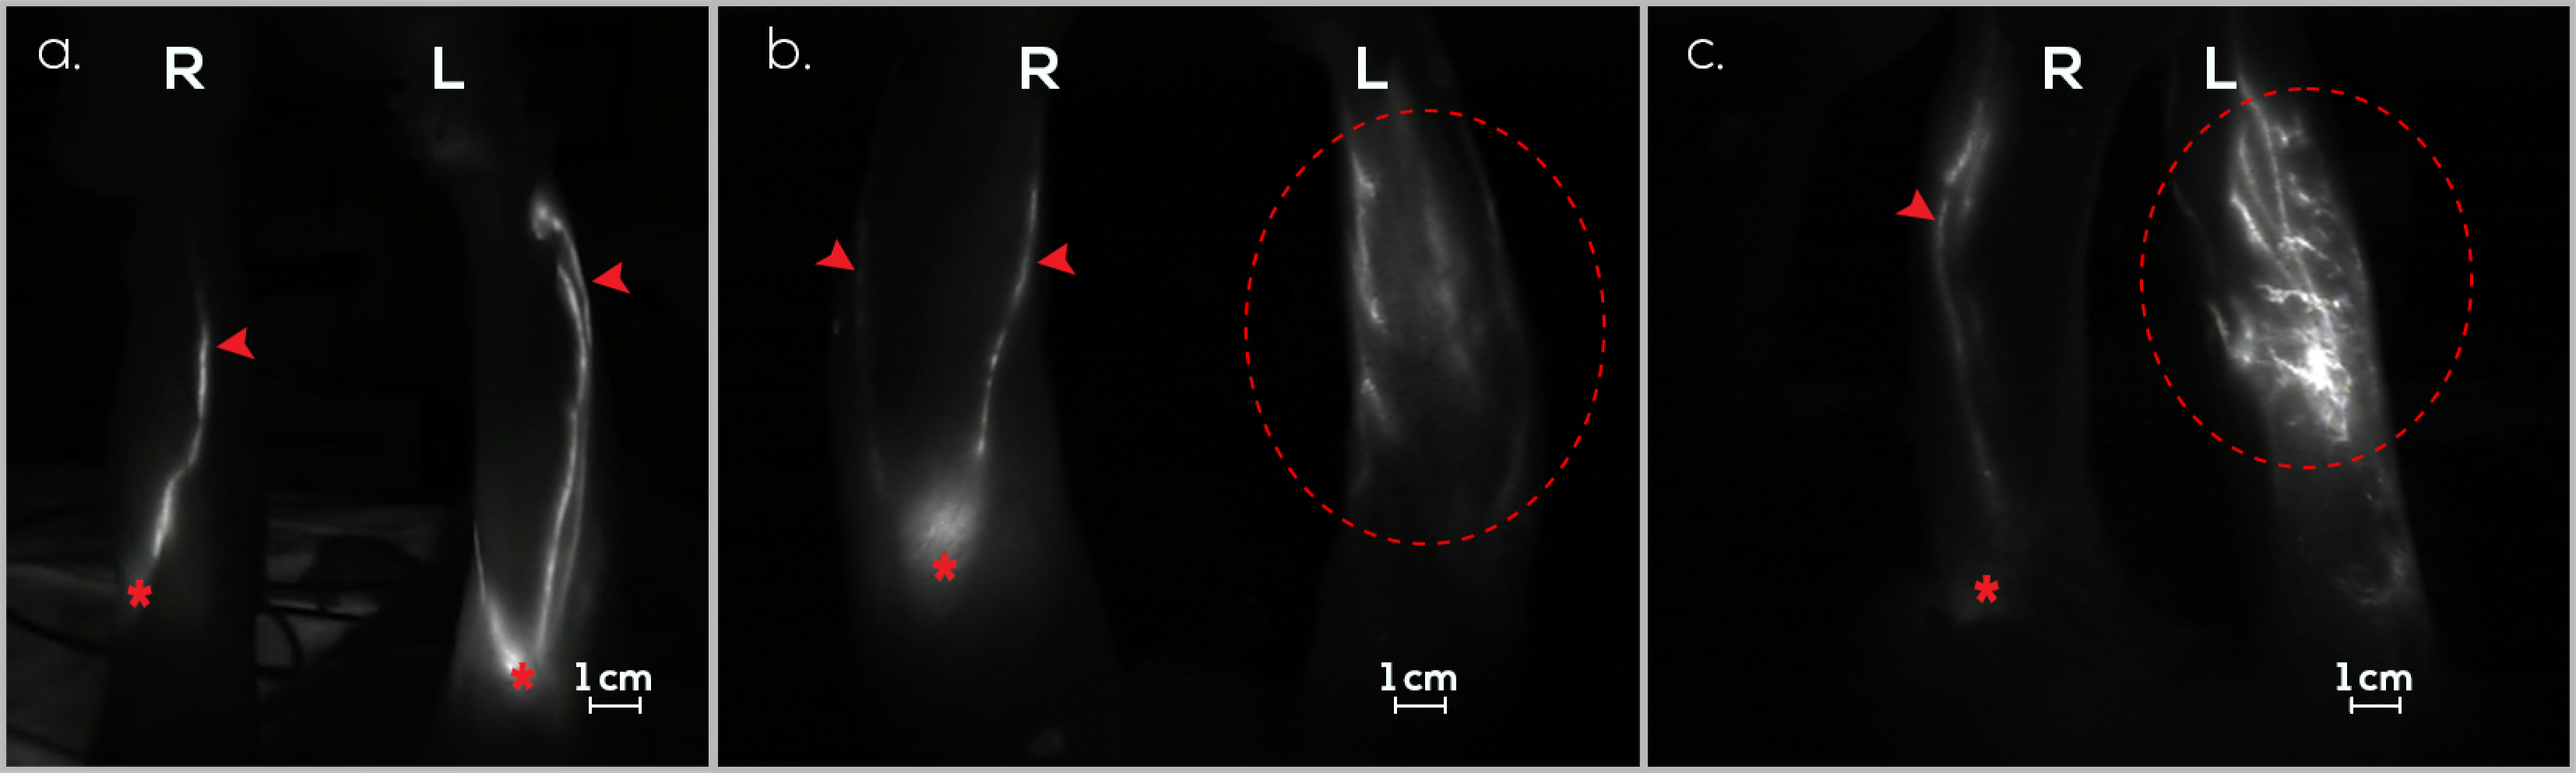

3.1. Treatment Group (G1)

3.2. Preventive Group (G2)

3.3. Control Group (G3)